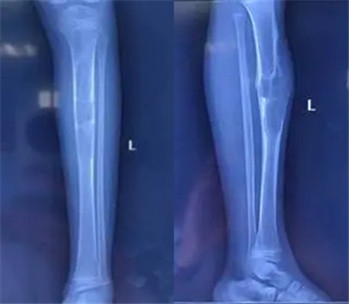

X线可见:长骨骨干处的偏心性、多房性骨质破坏区,边界清楚。

病变区多呈圆形或椭圆形,长轴与骨干平行。

周围可有轻度硬化边,无骨膜反应。

手术方案:左胫骨上段骨肿瘤切除、髓腔刮除植骨、取对侧腓骨植入缺损区,钢板内固定术

手术室内,气氛紧张而凝重,闫主任全神贯注,凭借着高超的医术和丰富的经验,精准地操作着每一个步骤。手术取得了圆满成功,术后的病理结果也再次证实了非骨化性纤维瘤的诊断。